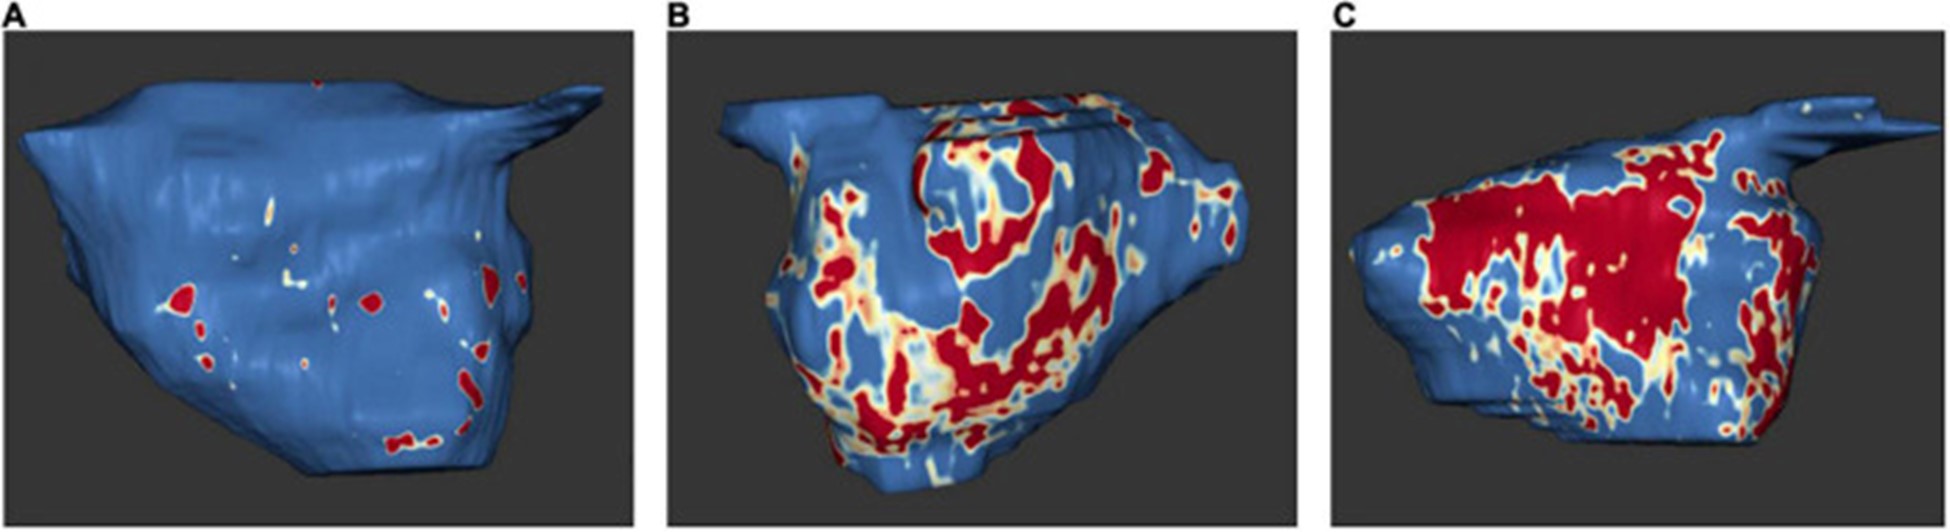

2009 年,Oakes 等人。建立了犹他阶段模型来量化 LA 纤维化 。根据该模型,将严重程度分为四个级别:犹他州 I,定义为 ≤ 5% LA 壁增强,犹他州 II,5–20%,犹他州 III,20–35%,犹他州 IV,>35% (图 5)。

图 5:左心房 MRI 检查示例:基于 3D 延迟增强磁共振成像扫描的左心房组织纤维化。正常左心房壁以蓝色显示,纤维化改变以红色和白色显示。纤维化量占左心房壁总体积的百分比。(A)犹他州第一阶段 (1%)。(B)犹他州第 3 阶段 (27%)。(C)犹他州第 4 阶段 (36%)。在 Misagh Piran 博士(Herz- und Diabeteszentrum Nordrhein-Westfalen,Ruhr-Universität Bochum)的友好支持下。